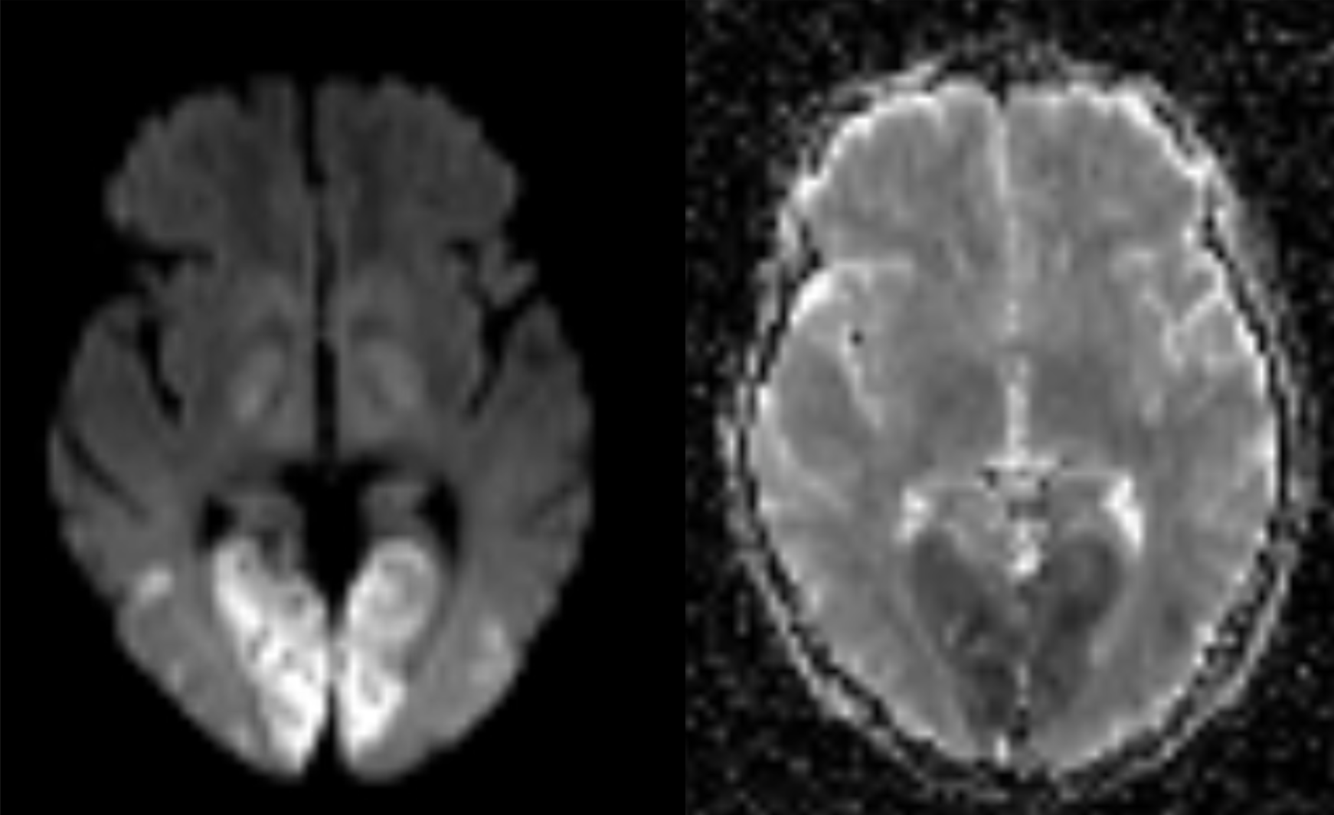

65 y/o M with dementia.

Creutzfeldt-Jakob Disease (CJD)